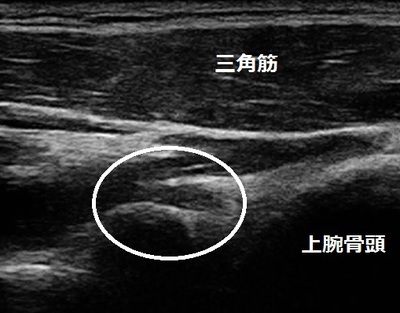

右肩関節後方 超音波画像

鶴ヶ島市 高校球児 投手。 右肩関節の痛み、野球かた(ベネット損傷+関節唇損傷)。

当院で超音波検査を行ったところ、右肩関節後部にベネット骨棘と関節唇の損傷が認められました

(画像丸の囲み)が、投球不能な痛みの原因ではありませんでした。

【治療】

骨棘や関節唇の損傷があっても投球は可能になります。ただし、整体やマッサージでは痛みは

消失しません。全身症状の適切な判断と治療方法が必要です。